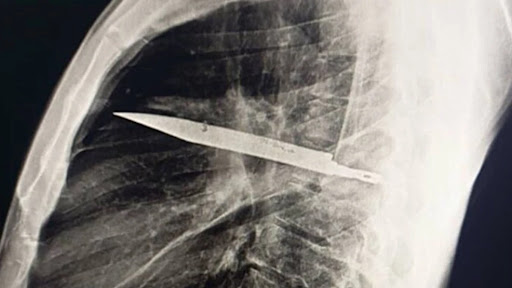

Sokkoló röntgen: kést találtak a férfi testében.